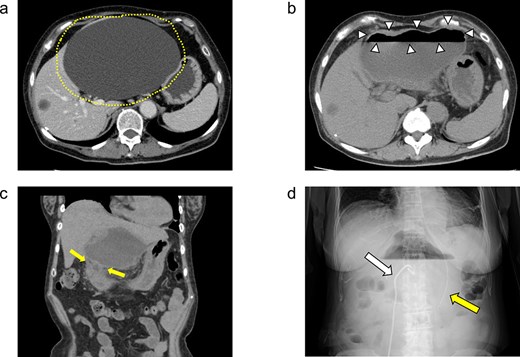

A 71-year-old female had suffered from upper abdominal pain for ~7–8 years. She consulted her primary care physician, and computed tomography (CT) demonstrated a 16-cm hepatic cyst in the left hepatic lobe (Fig. 1a). Although she had no history of peptic ulcer, she had not gotten an upper gastrointestinal endoscopy for decades.

(a) Enhanced CT images findings obtained in the examination by the patient’s primary care physician. A 16-cm hepatic cyst in the left hepatic lobe area was observed. Dotted line: The hepatic cyst. (b, c) Plain CT images findings obtained at the patient’s hospitalization. (b) This axial section shows the large hepatic cyst in left hepatic lobe area, which was collapsed and contained air bubbles. There were no findings of free air or leakage into the peritoneal cavity. Arrowheads: The air bubbles of collapsed large hepatic cyst. (c) A low-density area between the hepatic cyst and the duodenum with a suspicion of a fistulous tract can be seen on this coronal section. Arrows: The low-density area between the hepatic cyst and the duodenum. (d) An abdominal X-ray finding after the percutaneous catheter aspiration of the hepatic cyst with a 7Fr pig-tail catheter (left arrow). Right arrow: The nasogastric tube.

She exacerbated her upper abdominal pain and was transferred to our hospital. The laboratory workup (Supplementary Figs S1 and S2) showed that her white blood cell count and CRP level were high at 13 300/μl (92.5% neutrophil count) and 41.72 mg/dl, respectively. CT revealed a large hepatic cyst in the left hepatic lobe that was collapsed and contained air bubbles. There were no findings of free air or leakage into the peritoneal cavity (Fig. 1b). The CT also identified a low-density area between the hepatic cyst and the duodenum; a fistulous tract between them was suspected (Fig. 1c).

She was started on antibiotic therapy, and the hepatic cyst was punctured percutaneously with a 7Fr pig-tail catheter (Fig. 1d), and the elevated inflammatory response in blood tests gradually improved.